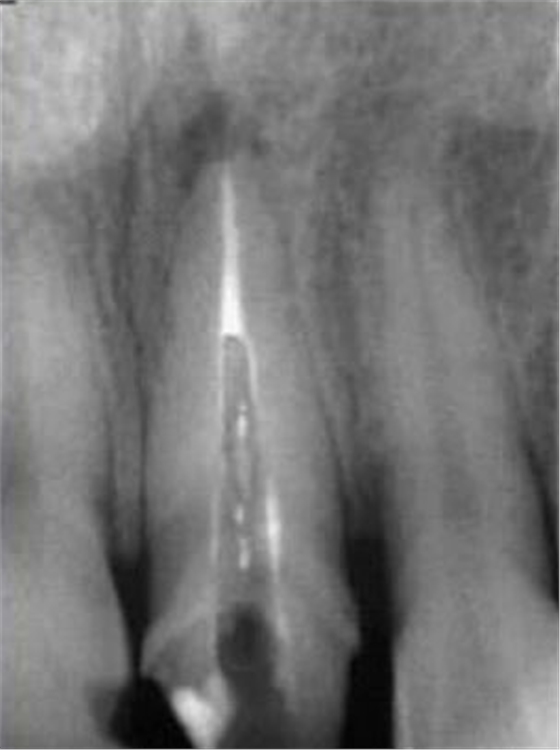

大多數(shù)醫(yī)生在樁道預(yù)備時(shí)習(xí)慣于干燥預(yù)備根管(圖 1),這樣很容易破壞根管壁的牙本質(zhì)結(jié)構(gòu),同時(shí)也可形成較厚的玷污層,影響樹脂水門汀與牙體組織的粘接。因此,臨床操作時(shí)應(yīng)選擇沖洗的方法冷卻預(yù)備根管(圖 2),防止牙膠及封閉劑粘連附著于根管壁形成第二玷污層(根管治療時(shí)形成的玷污層稱為第一玷污層),有利于樹脂水門汀與根管牙本質(zhì)的粘接。

圖1:干燥預(yù)備根管。 圖2:沖洗預(yù)備根管。